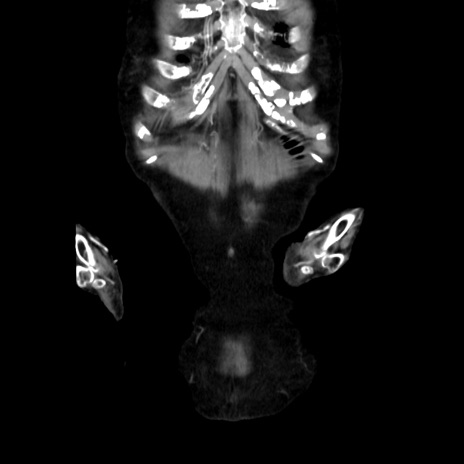

横断像